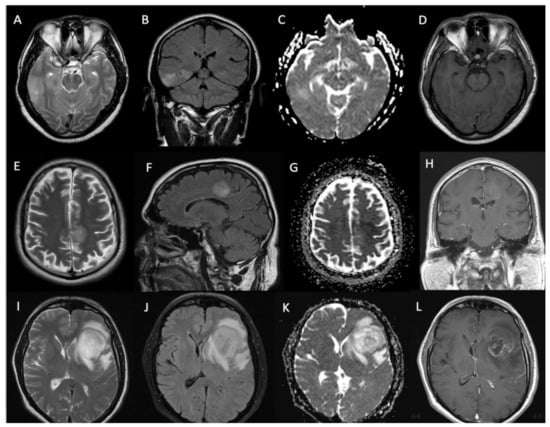

3.3. Imaging Characteristics

| Radiological characteristics | Numbers (percentage) |

| Location (n = 54) | |

| Lobar | 46 (85%) |

| Deep-seated | 8 (15%) |

| Contrast enhancement | |

| Solid pattern | 18 (33%) |

| Rim enhancement | 17 (31%) |

| Non-enhancing | 19 (36%) |

| Contrast enhancement on diagnostic MRI (present vs. absent) | 15.2 (12.1 to 18.3) vs. 28.8 (21.3 to 36.2) months | p = 0.003 |

| Location of the lesion on MRI (superficial vs. deep) | 18.3 (15.3 to 21.2) vs. 14.9 (12.7 to 17) months | p = 0.32 |

| Pattern of gadolinium enhancement (solid/patchy versus rim-enhancing with central necrosis) | 15.9 (12.5 to 19.3) vs. 14 (11.7 to 16.2) months | p = 0.57 |

| Pre-operative tumor volume on MRI (dichotomized at median—66.5 cc) | 20 (15.6 to 24.2) vs. 15 (12.3 to 17.6) months | p = 0.20 |

| ADC value (dichotomized at median—1.45) | 15.2 (11.4 to 19) vs. 19.8 (17.3 to 22.3) months | p = 0.43 |